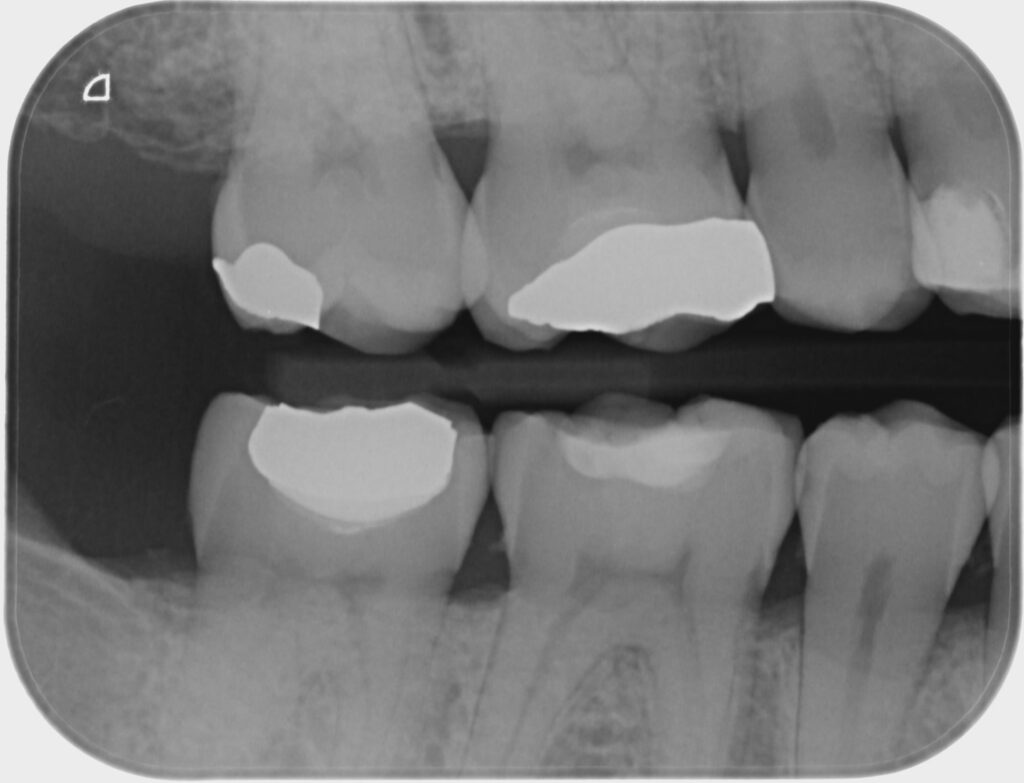

Bitewing xrays show the crowns of the posterior teeth and the height of the alveolar bone and Do Bitewing X Rays Show Wisdom Teeth The patient bites down on a little tab or wing that holds the. Acquire more information about jaw issues and missing or extra teeth; Help identify abscesses, cysts, and tumors;. Looks like you need a bite wing as opposed to pieces of a pano film, because the distal of #31 looks highly suspicious of having a cavity because of the. Do Bitewing X Rays Show Wisdom Teeth.

Decay on bitewing Twinkle Family Dentalcare Do Bitewing X Rays Show Wisdom Teeth They are the best tool to use for detecting cavities that are in between. Bitewings can also show areas of bone loss around teeth — a sign of periodontal disease; However, they are not taken for that. Looks like you need a bite wing as opposed to pieces of a pano film, because the distal of #31 looks highly suspicious. Do Bitewing X Rays Show Wisdom Teeth.

Bitewing xray with cavities 2 Palms Dentist, Shirley Christchurch Dentists Do Bitewing X Rays Show Wisdom Teeth The patient bites down on a little tab or wing that holds the. Acquire more information about jaw issues and missing or extra teeth; They are the best tool to use for detecting cavities that are in between. However, they are not taken for that. Help identify abscesses, cysts, and tumors;. Bitewings can also show areas of bone loss around. Do Bitewing X Rays Show Wisdom Teeth.